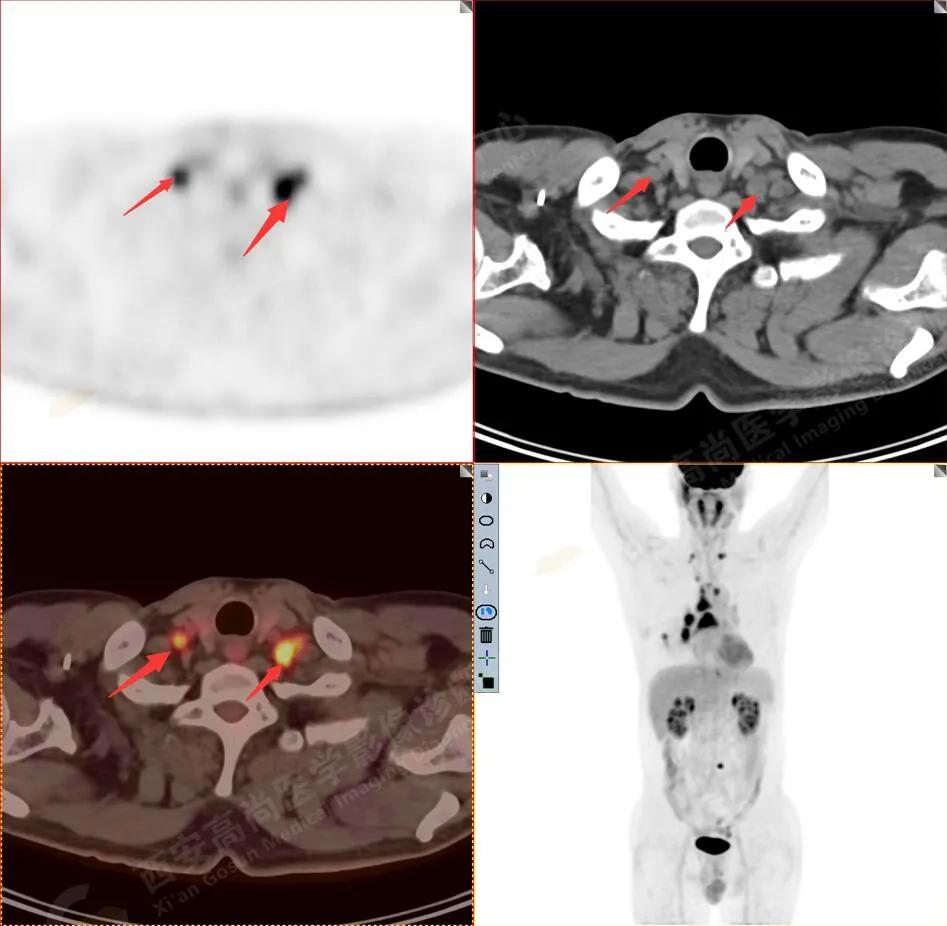

双测锁骨上淋巴结转移

3.右侧肺门、纵隔(1L、1R、3A、4、6、7组)及双侧锁骨上多发肿大淋巴结,呈不同程度FDG代谢异常增高,考虑为淋巴结转移。